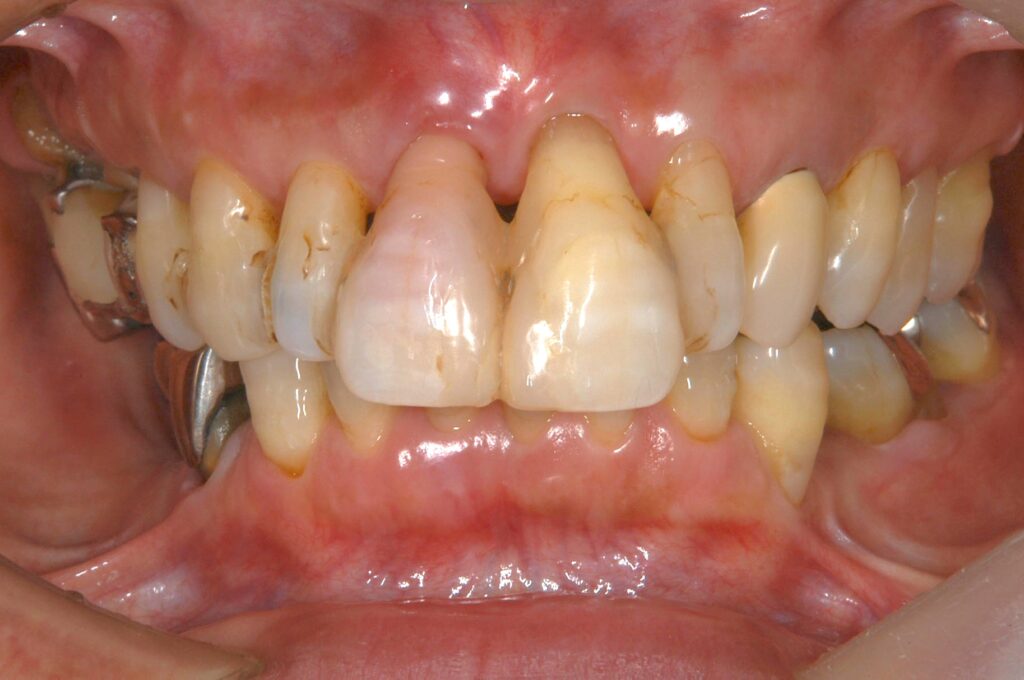

主な診断は、歯周病・虫歯・審美障害・不良補綴物・不正咬合・歯肉退縮です

初診